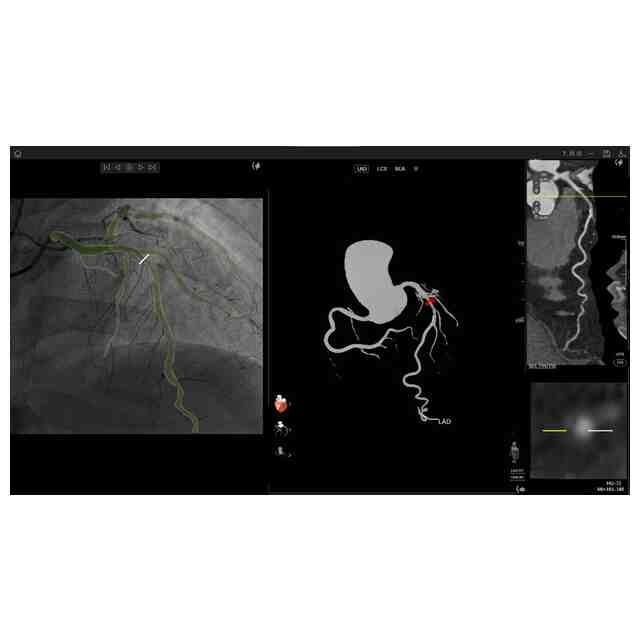

画像図及び変化後を示す画像図1~3は、例えば、複数の医療用画像を登録した後に表示して分析するために用いられる。使用状態を示す参考図1~6、変化後を示す画像図1の使用状態を示す参考図1~5、変化後を示す画像図2の使用状態を示す参考図、及び、変化後を示す画像図3の使用状態を示す参考図は、医療用画像データを分析するに際し、表示される図を示したものである。変化後を示す画像図1は、画像図における下方において黄色で示されたウインドウの右上隅にある「非表示」ボタンが押されると表示される画像である。変化後を示す画像図2は、変化後を示す画像図1における黄色で示された左端のウインドウがダブルクリックされると表示される画像であり、変化後を示す画像図2における黄色で示されたウインドウがダブルクリックされると画像図に戻る。変化後を示す画像図3は、画像図における黄色で示された中央のウインドウがダブルクリックされると表示される画像である。

図面中、黄色で示された部分以外の部分が部分意匠として意匠登録を受けようとする部分である。